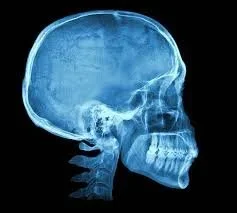

Brain Repair with NAC Supplement

A new study has shown that a simple, cheap over the counter supplement can have regenerative and life-saving benefits for the brain in just ONE WEEK.